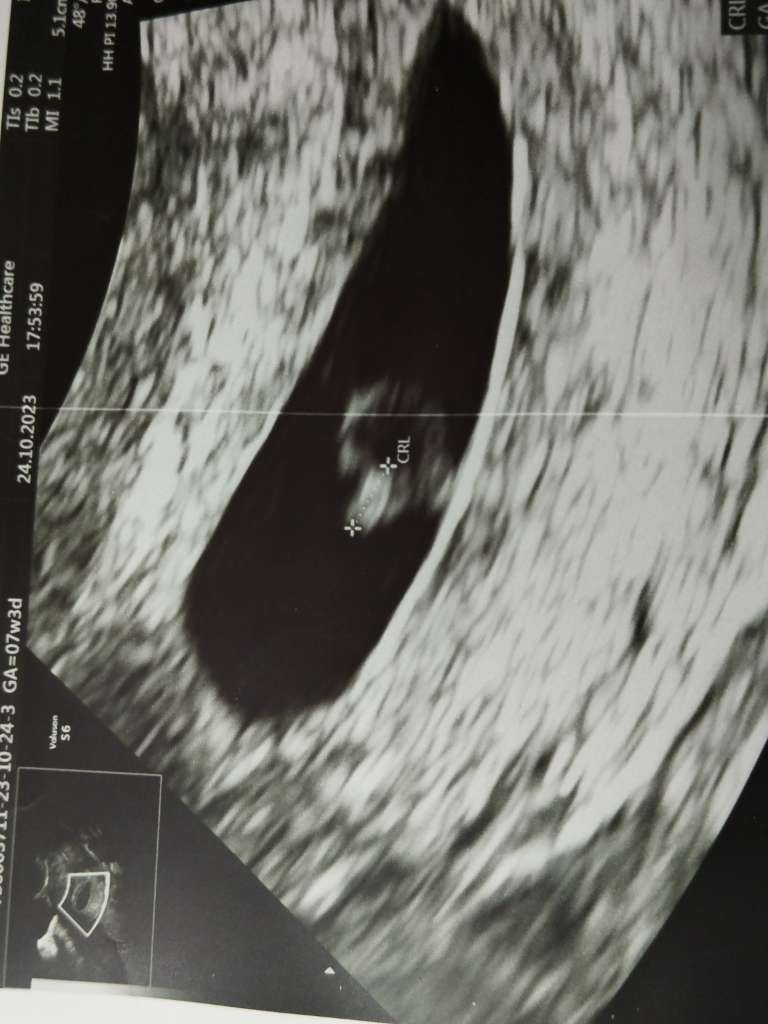

Tutaj macie zdjecie do galerii:)

Załączniki

• ad9fc828-07d2-4e3f-9b2c-f10c38ef7149.jpeg

ad9fc828-07d2-4e3f-9b2c-f10c38ef7149.jpeg

59,7 KB · Wyświetleń: 99